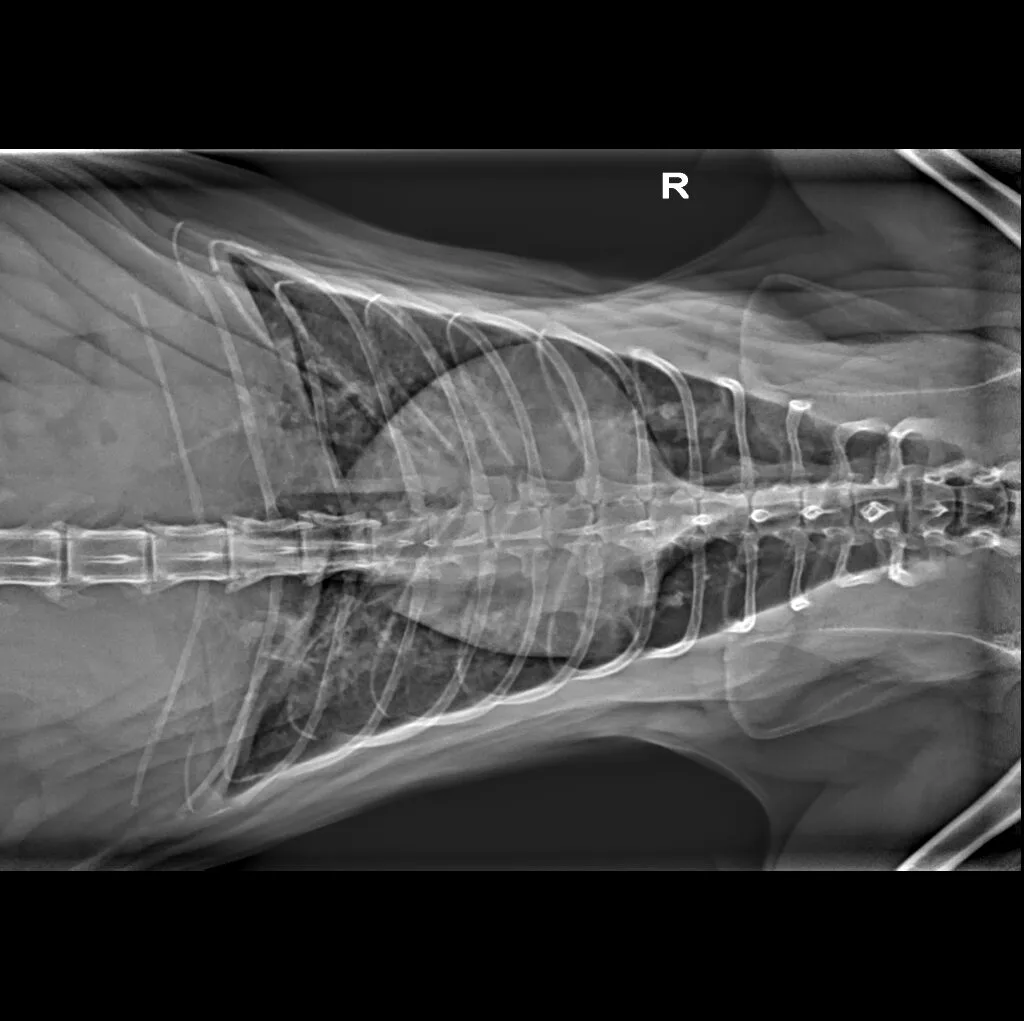

🔹 Cardiac & Respiratory Conditions – Evaluating heart disease and lung disorders

Digital radiography offers superior imaging quality and precision compared to traditional X-ray techniques. It allows us to detect hidden health issues early, leading to faster and more effective treatments.

At Grand Ave. Pet Hospital, we utilize digital radiography to diagnose and monitor a wide range of medical conditions in pets. Digital X-rays provide clearer images, faster results, and safer radiation levels, ensuring the best possible care for your furry companion.